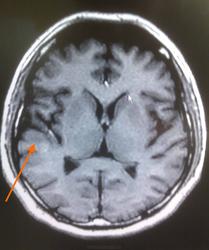

ID:53441

Подводник в каком смысле? Может проявления кессонной болезни? Не видел ни разу, но в принципе...

Сказал, что плавал на подводной лодке

Может быть , очаговые проявления на фоне иммунодефицита , а здоровьем пышет до поры до времени

Не может быть РС? Очаги юкстакортикальные.

РС не не похоже. Мне кажется здесь однозначно на контраст вводить. Может инфекция цнс? Паразитарная например цистицеркоз ? А где он путешествовал?

Неплохо бы законтрастировать. По отдельности кажда зона может тянуть на очаг постишемической природы, все вместе в разных бассейнах - как-то сомнительно. А на контрасте и паразиты могут быть видны и туберкулёзные гранулёмы, да хоть и активные очаги РС (хотя сомневаюсь, что это он).

Церебральный токсоплазмоз может быть?

Один очаг (в виске) умеренно и равномерно накопил контраст... Новых очагов при контрастировании не выявилось.

По поводу "подводника" - плавал на подводной лодне, несколько раз были аварийные резкие всплытия.

Вообще-то, похоже на демиелинизацию. А что другие отделы мозга - больше нет нигде?

Да, похоже на демиелинизацию, по почему локализация такая и с чем она связана? Больше нигде никаких очагов, базальные ядра без очагов...